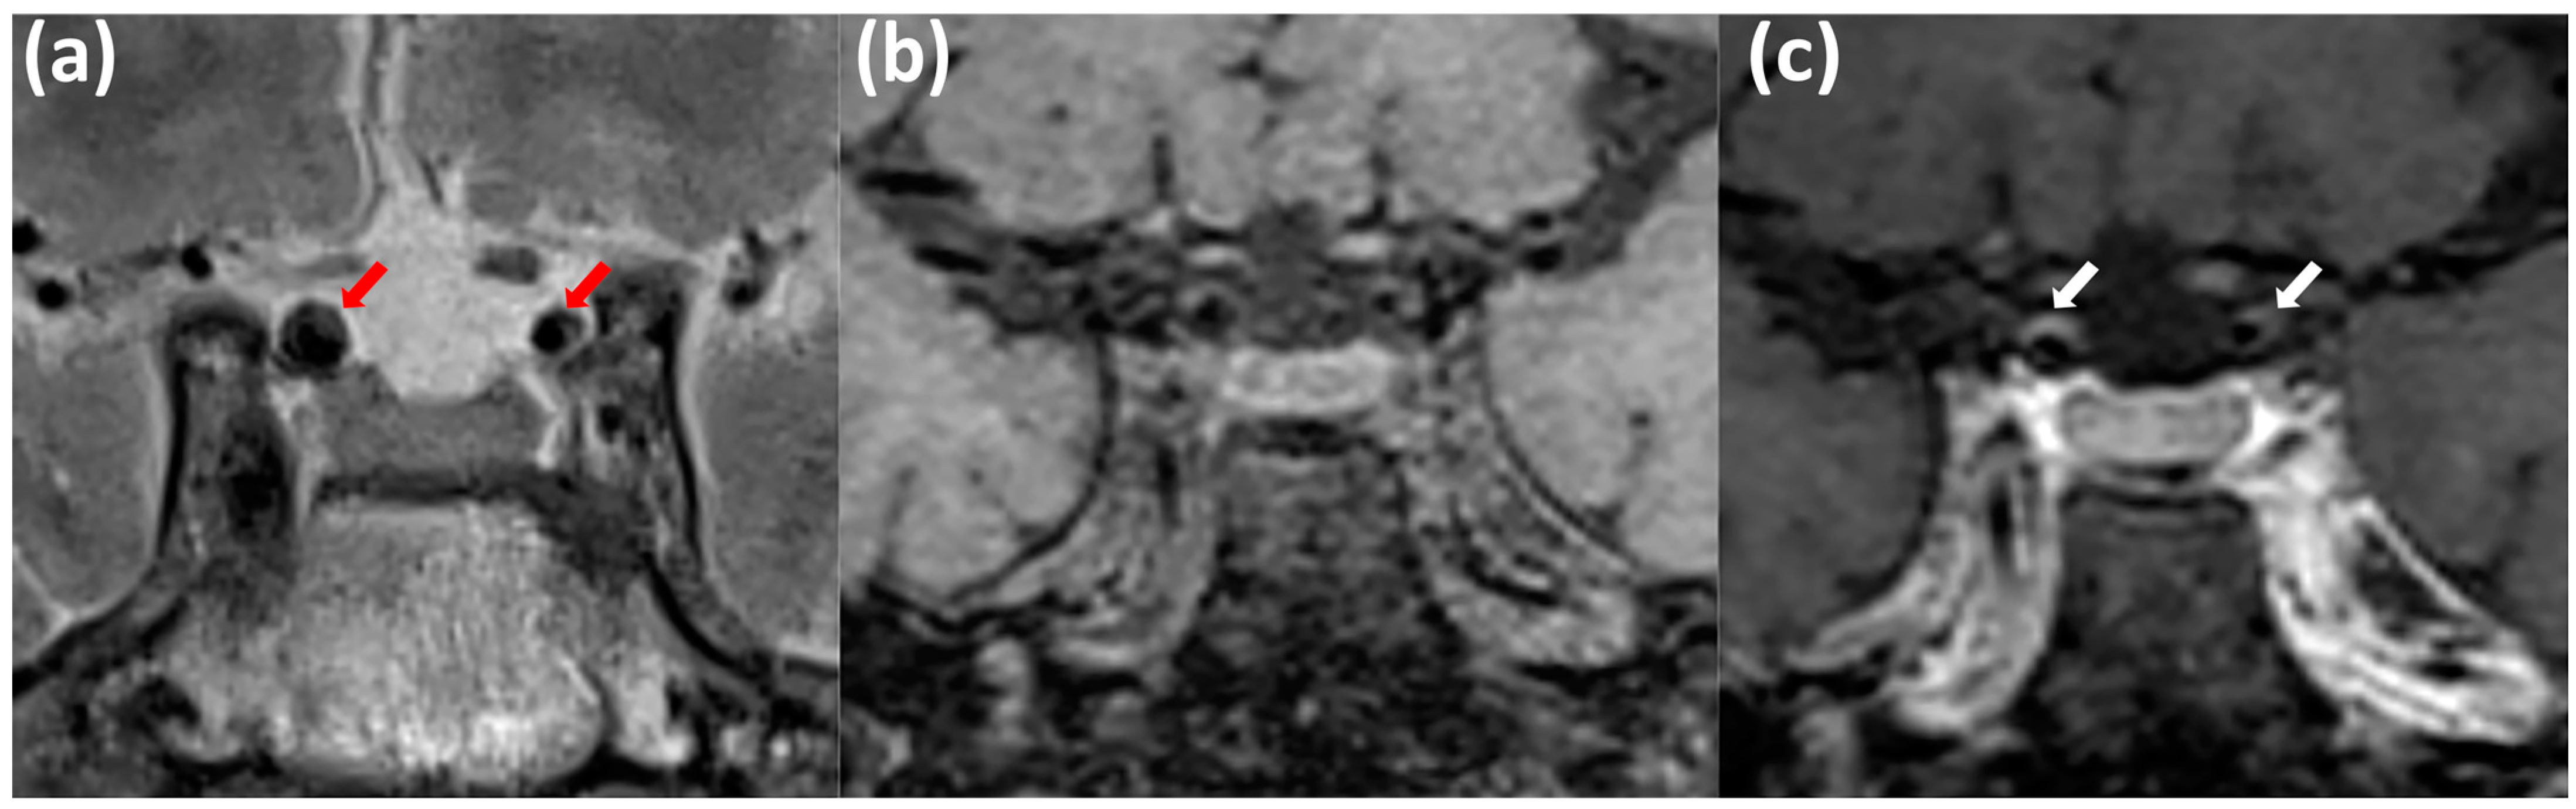

2. Materials and Methods

2.1. Study Population